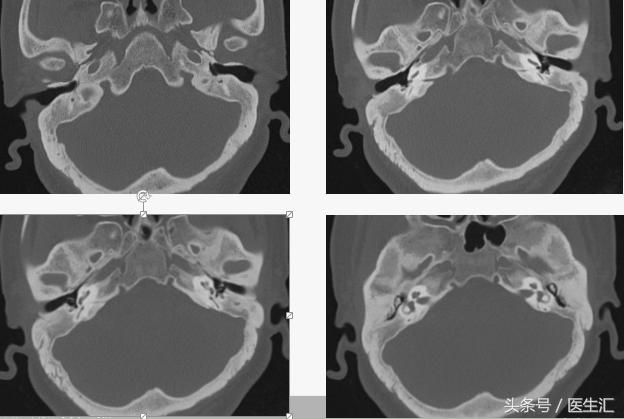

颞骨CT:

初步诊断:

•慢性化脓性中耳炎(左,单纯型)

•鼓室硬化(左)